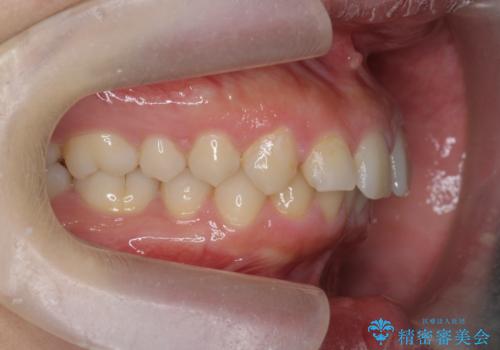

深い噛み合わせ、すきっ歯の改善 ワイヤーを用いたマルチブラケット矯正

- 噛み合わせが深く、前歯が突き出て隙間が出てきたことの改善を希望され矯正治療の相談で当院に初診来院されました。

ワイヤーを用いたマルチブラケット矯正を行うことで深い噛み合わせを改善し、前歯の隙間もなくし審美的な歯列へと治療をおこなっていきます。